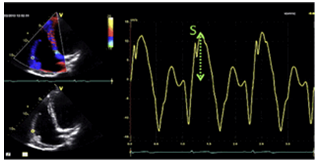

RV纵向收缩功能:

S/ S’( 三尖瓣环收期峰值速度)